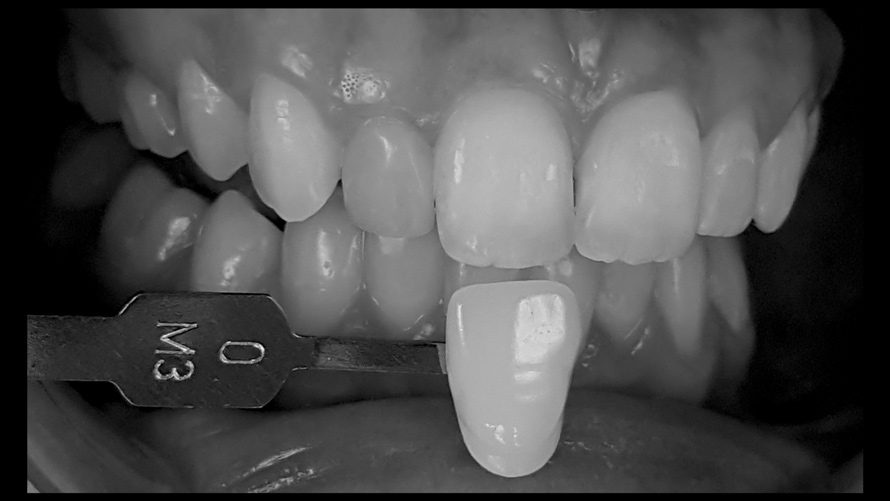

Shade Selection and Laboratory Communication

The most utilized intraoral photographs in the field of dentistry are perhaps those that capture shade information (Figure 18 and Figure 19). The analysis of color (ie, value, chroma, hue) in dentistry is a critical step in the fabrication of esthetic indirect restorations, such as all-ceramic crowns and porcelain laminate veneers. The ability to properly communicate this information with the dental laboratory is essential to ensure an appropriate shade match, a reduction in chairtime and overhead, and most importantly, a satisfactory patient experience and treatment outcome. In recent years, the use of polarized light photography as an aid in the shade selection process has become extremely popular. For some EALS devices, special polarizing filters have been specifically designed to fit over the light-emitting portion of the device (Figure 20 and Figure 21). The images produced using polarized light photography demonstrate an elimination or reduction in the specular reflection of hard and soft tissue, resulting in a matte-finish appearance of the dentition and gingiva. These types of photographs aid the ceramist in identifying areas of opacity and translucency, crack lines, hypo- or hypercalcification, and other internal features of the dentition that may not be readily visible without such a filter (Figure 22).

(18. and 19.) Tooth shade analysis of value, chroma, and hue taken with a smartphone and an EALS device.

Figure 18

Figure 19